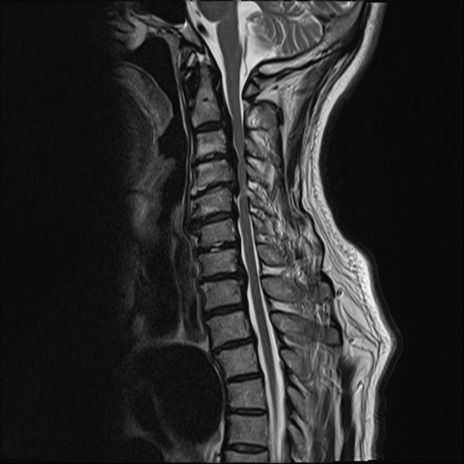

頚椎MRI

T1WI(矢状断像)

T2WI(横断像)

矢状断像と横断像